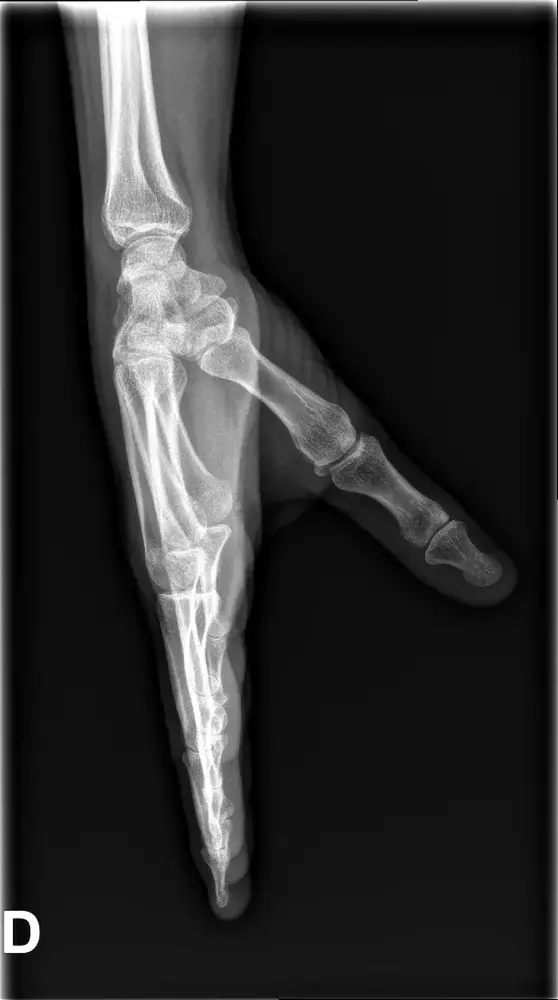

- fractures